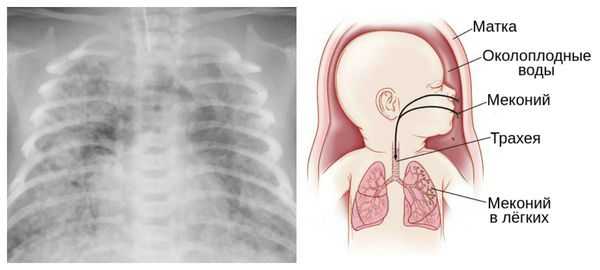

Главное — значительно увеличивается вероятность мертворождения: в 40 недель это 2-3 случая на 1000 родов, после 42-х недель — 4-7 случаев. Происходит старение плаценты, снижается количество околоплодных вод. В них может попасть меконий — первородный кал, который в норме должен отходить у младенца уже после родов. Попадая в дыхательные пути, мекониальные воды могут привести к проблемам с легкими у новорожденного.

Из-за снижения кровотока в почках плода выделение мочи значительно уменьшается, развивается маловодие. Также изменяется характер околоплодных вод: они теряют прозрачность, становятся мутными, приобретают желтоватый или зеленоватый оттенок из-за примеси мекония — первых фекалий ребёнка.

Осложнения перенашивания беременности

Для плода большую опасность представляет асфиксия (острая гипоксия) и отслойка плаценты. Нехватка кислорода внутри утробы стимулирует плод выполнить несвоевременные дыхательных движения. Они приводят к заглатыванию вод и возможному воспалению лёгочной ткани — пневмониту. Если в водах есть примесь мекония (первородного кала), то велика вероятность мекониальной аспирации — проникновения содержимого кишечника новорождённого в его лёгкие.